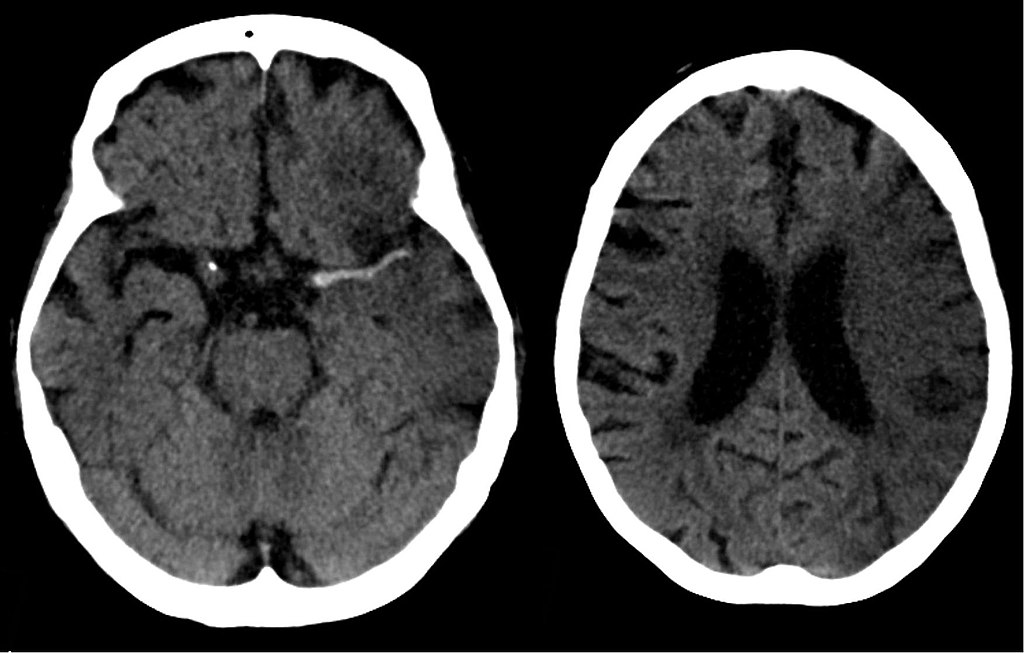

Global Cerebral Ischemia

Global cerebral ischemia is ischemia that effects the entire cerebral tissue.

Important causes of global cerebral ischemia include:

- Minimal perfusion (e.g. atherosclerosis)

- Abrupt reduction in blood flow (e.g. cardiogenic shock)

- Persistent hypoxia (e.g. anemia)

- Hypoglycemia episodes (e.g. insulinoma)

Clinical findings of global cerebral ischemia depend on the length and severity of the trauma.

- Mild global ischemia causes momentary confusion that quickly goes away

- Severe global ischemia causes diffuse necrosis and may result in a vegetative state condition

- Infarcts in watershed regions which may effect memory, sensory, and motor functions